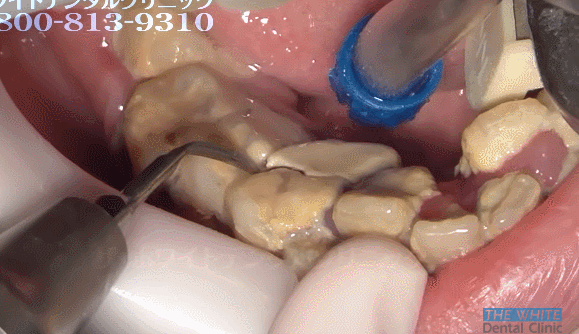

25세 여성의 치석제거. 분명히 난감이라고 말했습니다 (난감주의)

와우... 스케일링할때 피 엄청 나겠다

치아 제거 수준 ,,,

잇몸 진짜 다 내려앉겠다,,,

스켈링 4번에 나눠서 하셔야 할 각...

양치를 안하신건가? 저렇게 심각하면 진작 치과가시지 저정도면 바로 보일정도인데...

와... 치열 안좋아도 양치만 제대로 하면 안생기지 않나요...

치아 위에 잇몸도 치석때문에 부은건가요? 아파보여요 ㅠㅠ

저건.. 원장님이 큐렛도 해주셔야...ㅎㅏ...끔찍

저정도면 아프겠다

퉁퉁 부었네...아이고

아우,,, 하시는 분 손목 나가시겠는데요,,,

헐 저정도로 깊게 많이 생기면 오히려 치과에서 하지 말라고 권장하지 않나요ㅜㅜㅜㅜ 잇몸 다 상할텐데..

입냄새 대박이었을거같아요...

근데 저런 분들 꽤 있어용 교합면까지 치석 덩어리인...

거의 치아 옆에 치아 난 느낌

근데 어떻게 해야 저정도까지 치석이 쌓일 수 있는거에요 ?

저정도면..치조골 완전...와우....